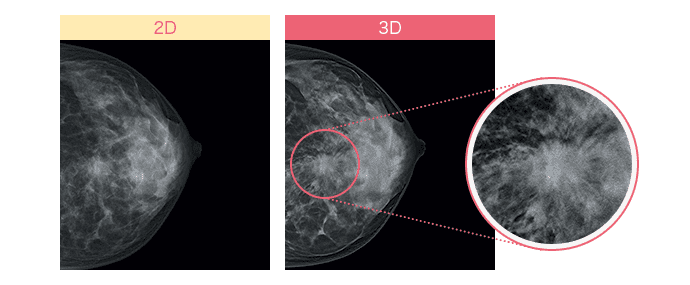

さらに進んだ「3Dマンモグラフィ(トモシンセシス)」とは?

従来のマンモグラフィ画像は、平面の撮影(2D)のため乳腺と病変が重なると、判別が難しく正確な診断に時間を要することがあります。

しかし最近では乳房内の構造をより正確に描出できる「3Dマンモグラフィ(トモシンセシス)」が登場して、より高い精度で乳がん検査を行うことが可能になりました。異なる角度から乳房の画像を複数撮影し、それを再構成して乳房の断層像を生成することで、乳腺の重なりが除外でき、これまで発見が難しかった病変の観察がしやすくなりました。*4